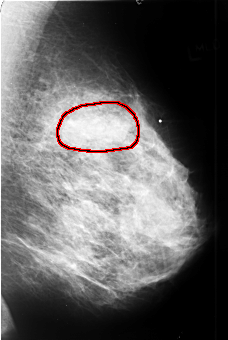

B_3409_1.LEFT_MLO

LEFT_MLO LINES 4408 PIXELS_PER_LINE 2960 BITS_PER_PIXEL 12 RESOLUTION 50 OVERLAY

FILE: B_3409_1.LEFT_MLO.OVERLAY

TOTAL_ABNORMALITIES 1

ABNORMALITY 1

LESION_TYPE MASS SHAPE LOBULATED-IRREGULAR MARGINS OBSCURED-ILL_DEFINED

ASSESSMENT 4

SUBTLETY 4

PATHOLOGY MALIGNANT

TOTAL_OUTLINES 1

BOUNDARY